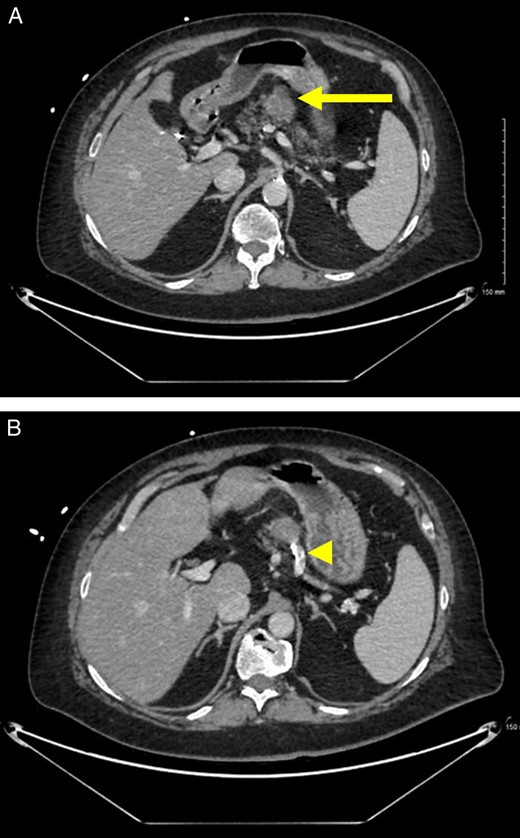

A 60-year-old woman with underlying hypertension, type 2 diabetes mellitus on insulin, gastroparesis, sinoatrial block status post cardiac pacemaker, gastroesophageal reflux disease, and prior transient ischemic attack presented with hypertensive urgency, nausea, vomiting and left subcostal pain radiating posteriorly. The surgical oncology service was consulted when a CT scan revealed a pancreatic mass that had enlarged from imaging obtained eight years prior. More concerningly, this 3.4 cm, mid-body pancreatic mass now involved the splenic artery (Fig. 1). The patient recalled two previous endoscopic biopsies of the mass were non-diagnostic. Of note, she had an extensive past surgical history: cholecystectomy, congenital umbilical hernia repair, hysterectomy, and several bilateral knee surgeries which included patellar tendon repair, ACL repair, and meniscal repair.

Preoperative imaging. (A) CT scan with IV contrast demonstrates a lobulated, heterogeneous, exophytic, enhancing mass (arrow) in the mid-body of the pancreas. (B) There is abutment of a calcified splenic artery (arrowhead).